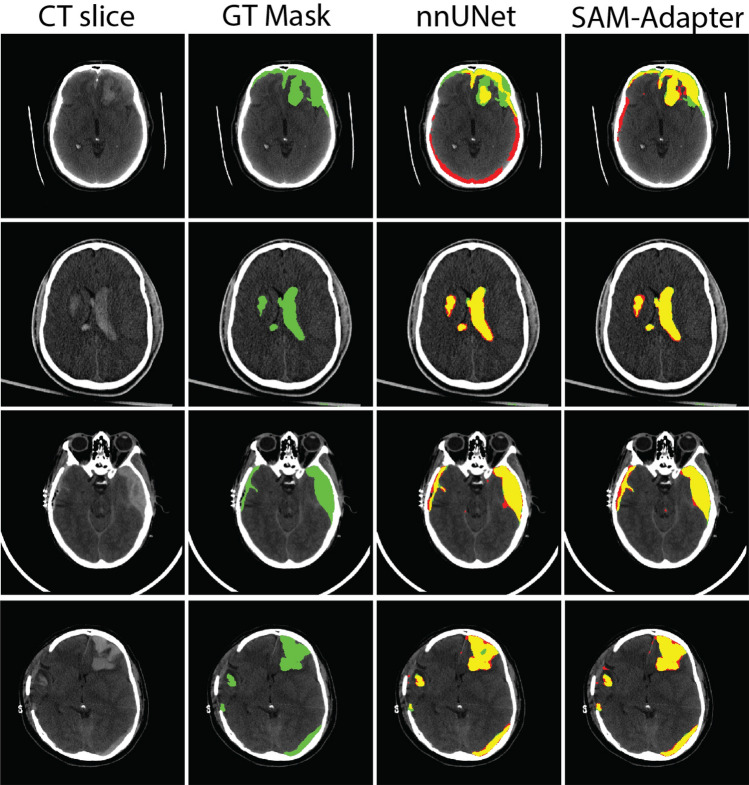

Hematoma segmentation in traumatic brain injury (TBI) is critical for accurate diagnosis and effective treatment planning. In this study, we evaluate various automated segmentation models, including stat-of-the-art architecture as benchmarks, and compare their performance with our proposed SAM-Adapter method for segmenting hematomas in brain CT scans. By incorporating the adapter into the vanilla SAM model, we address the challenges in medical imaging, which has very limited annotated datasets, enhancing model performance efficiency. We also find that domain-specific pre-processing, such as contrast adjustment, reduces the need for extensive pretraining, making the model more streamlined. And the model performance benefited with optimization and hyperparameter tuning. Our results demonstrate that the SAM-Adapter model achieved strong performance and reliability in identifying hematomas with Dice (72.34%), IoU (59.78%), 95% HD (5.57), sensitivity (75.39%) and specificity (99.73%). Inter-observer variability was assessed, revealing that the model's performance Dice (67.20%) was closely aligned with human expert agreement Dice (63.79%), suggesting its potential clinical utility. The external validation on the HemSeg-200 dataset, which contains 222 scans, demonstrates the robustness of our approach across diverse cases. These advancements in automatic segmentation hold promise for improving the accuracy and efficiency of TBI diagnosis, supporting clinical decision-making, and enhancing patient outcomes.